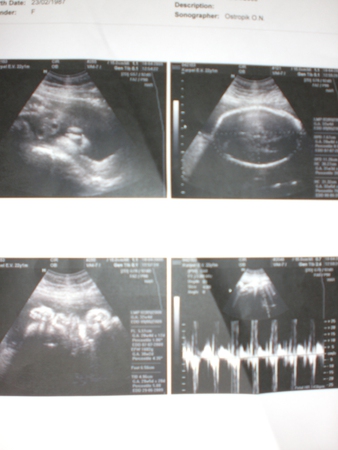

32 недели в животике - полет нормальный

32 недели в животике - полет нормальный